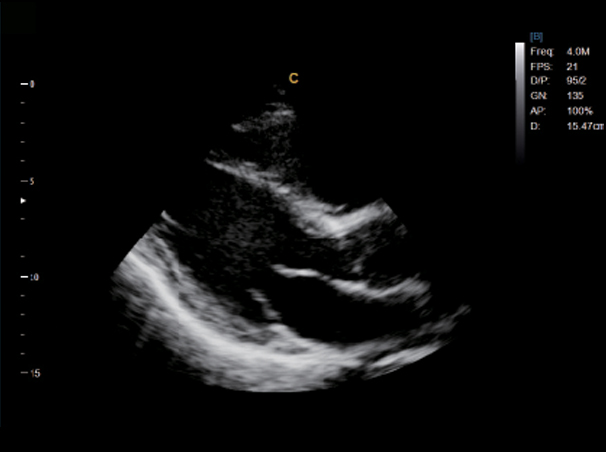

LV Longitude View, B Mode

Apical Four Chamber View, B Mode